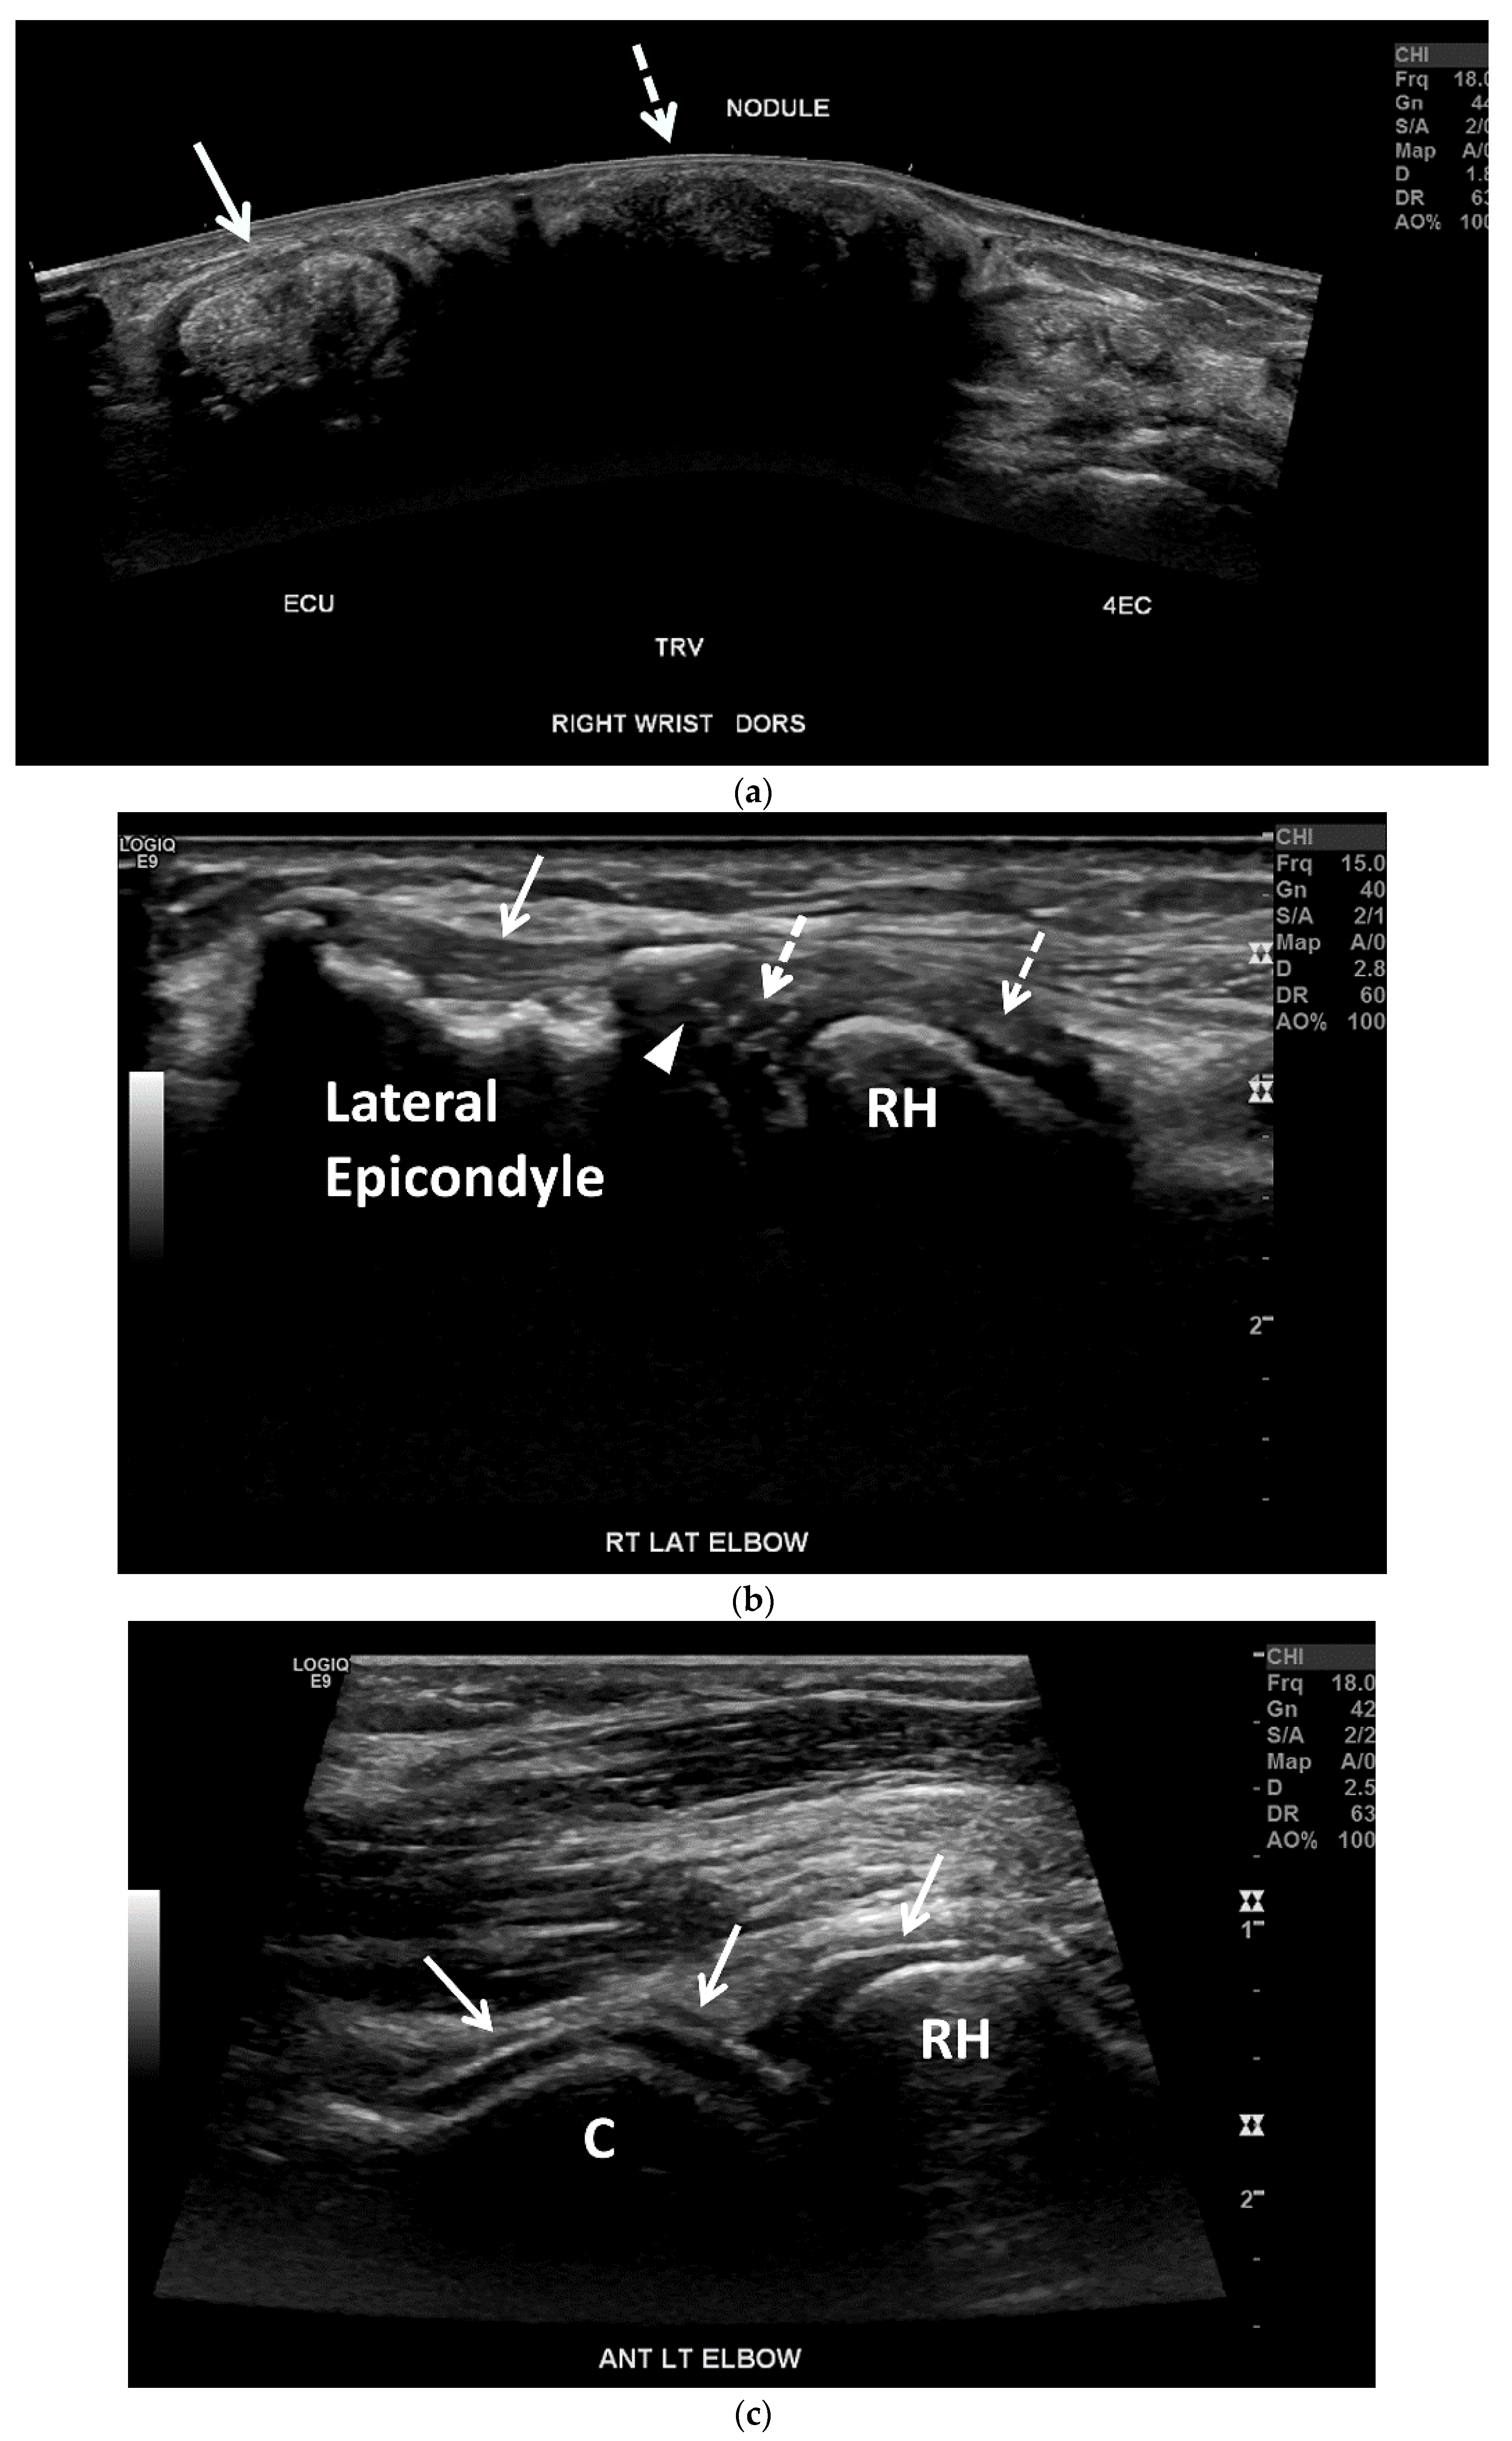

3.2. Ultrasound (US)